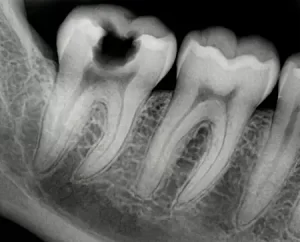

Определить заболевание возможно только по результатам диагностики: необходимо провести осмотр и опрос пациента, а также провести рентген. Решение о постановке диагноза принимает врач после комплексного обследования:

- Рентгенография. Позволяет распознать пульпит на снимке по ряду объективных признаков.